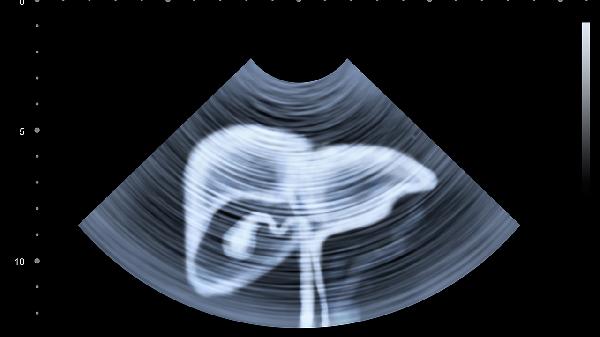

生理图库:月经推迟跟痛经有关系吗